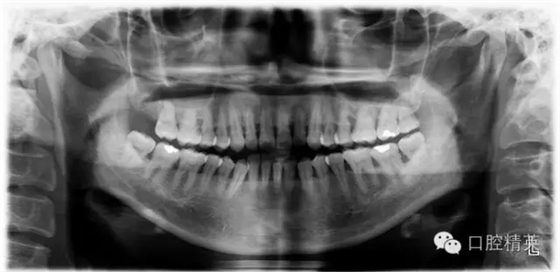

檢查見(jiàn)大量齦上及齦下結(jié)石,探診出血,牙周袋較深,32-42 II度松動(dòng)。X線片顯示牙槽骨水平吸收。

X-ray: